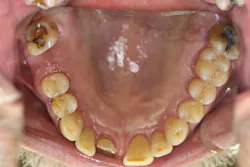

Upon receiving approval from his oncologist to commence with dental care three months later, his examination revealed the following (figures 1-5):

- Severe class III active periodontal disease

- Rampant, generalized cervical caries with some lesions quite extensive in nature

- Broken no. 8 (chief complaint)

- Broken/carious nos. 18, 19, and 30; caries on no. 2

- Generalized dry mouth with white patchy mucosa; he did have a complaint of having a “sticky mouth.” Note: When we took the photos, we had to put water in his mouth because it was so dry.

The genesis for his caries was evident–drug-induced dry mouth and time were the perfect storm for widespread infection that demanded immediate management. Suffice to say, my news to the patient was not welcome.